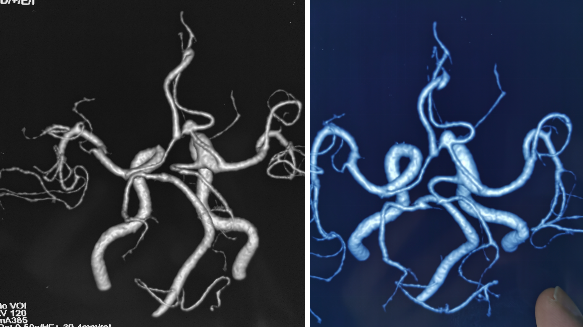

全脑血管造影:右侧大脑中动脉M1分叉处动脉瘤,瘤体3.3 mm*4.1 mm,瘤颈2.7 mm。前交通动脉瘤栓塞完全。

全麻满意后,常规消毒铺巾,采用改良 Seldinger技术穿刺右侧股动脉成功,置入6F动脉鞘。黑泥鳅导丝带领5F单弯导管行脑动脉造影,右侧颈内动脉造影见:右侧大脑中动脉M1分叉处动脉瘤,瘤体3.3 mm*4.1 mm,瘤颈2.7 mm。前交通动脉瘤栓塞完全。

诊断:右侧前交通动脉瘤

患者在全麻下、多参数监护仪监测下行前交通动脉瘤经右侧颈内动脉支架辅助下栓塞术。全麻后,常规消毒销巾,采用改良seldinger技术穿刺右侧股动脉或功,置入6F动脉鞘。黑泥鳅导丝及多功能导管带领6F MPD导管达到右侧颈内动脉岩段,行造影见∶前交通动脉瘤,瘤体3.5 mm*5.1 mm。在路图引导下,徵导丝(Synchro 0.014 in*200 cm)带领弹支架微导管(SL-10)到右侧大脑前动脉A2段,退出微导丝。微导丝(Synchro 0.014 in*200 cm)带领弹簧圈微导管(eV3 Echelon-10)到达前交通动脉瘤体内,退出微导丝。经弹簧圈微导管填入首枚弹簧圈(Codman COMPLEX XTRASOFT3 mm*6 cm)成篮良好,在路图引导下在支架管内输送支架(Neuroform Atlas 3.0 mm*21 mm)并释放完全覆盖动脉瘤颈,造影可见支架打开良好解脱首枚弹备圈,沿弹簧圈导管继续填入弹簧圈(可见护理记录单)间断造影确保双侧大脑前动脉血流通畅。右侧颈内动脉造影确认∶前交通动脉瘤填塞致密,双侧大应前动脉血流通畅。手术结束。右侧股动脉鞘处用血管封堵器(Coxrds Exoseal 6F)封堵,并压迫器持续压迫。木后患者清醒。

颅内动脉分叉处宽颈动脉瘤一直是介入治疗的一个难点,存在支架到位困难、介入栓塞术后复发率高的特点。大脑中动脉分叉部动脉瘤与前交通动脉瘤临床使用Neuroform Atlas新型支架,有望进一步提高支架到位与栓塞成功的比率。

Neuroform Atlas支架系统是Neroform支架的新一代产品,其改进后的设计可以使支架经更细的微导管输送(Atlas可以通过0.0165 inch内径的微导管输送,而以前的支架产品一般只能通过0.027 inch内径的较粗微导管输送)。较前代Neuroform支架相比,Atlas支架在操作上易输送,通过性强,易定位、释放,释放时张力小,无明显上下移位,贴壁性好,Atlas支架具有更佳的“脚手架”作用。